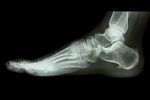

足底筋膜炎/足裏の痛み

【症例】足底筋膜炎

「足底筋膜炎」と言う難しい名前にビックリされているのかもしれませんが、痛みの仕組みを少し理解するとご自身で手当てをする事が可能です。

足裏は血液の循環が悪くなり酸欠を起こしている状態です。